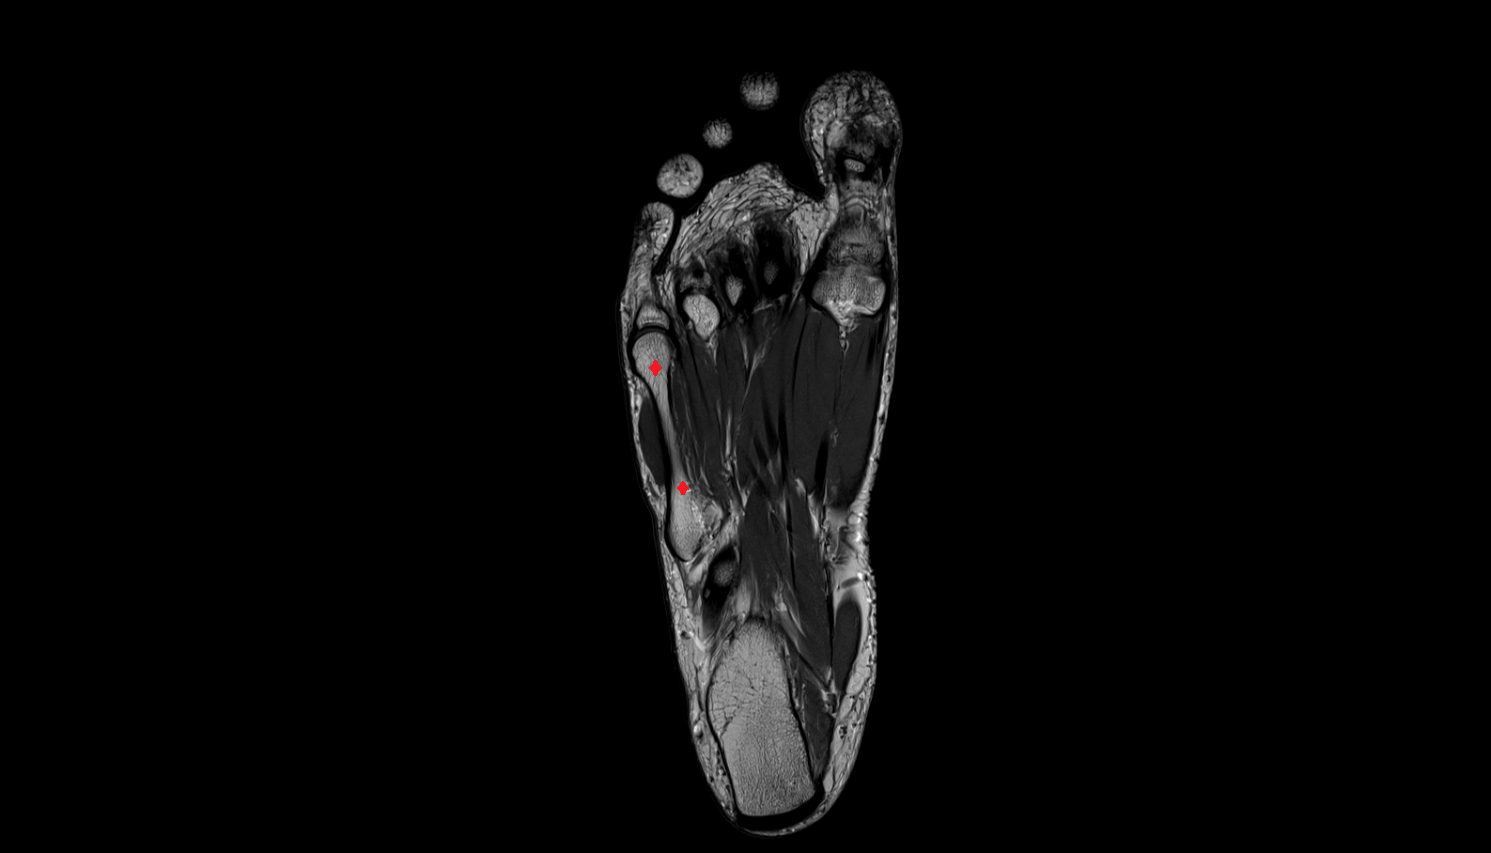

- Plantar aponeurosis